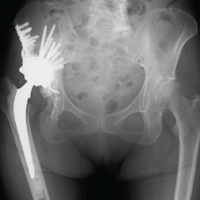

An 80-year-old right-hand dominant woman came to our clinic after a fall at home. She slipped while walking and landed squarely on her left arm. Pain was immediate and severe, and she was unable to raise the limb afterward. There was no loss of consciousness, seizure, or syncopal episode to suggest a systemic cause for the fall. Her medical history included well-controlled hypertension and early osteoarthritis of the knees. She had never sustained a fragility fracture and was not on corticosteroid therapy. On examination, she was comfortable, alert, and hemodynamically stable. The left arm showed diffuse swelling with a hint of angulation at the mid-arm level. The skin was intact, with no abrasions or breach. Palpation elicited marked tenderness over the midshaft of the humerus, with crepitus and abnormal mobility on gentle stress. Importantly, neurovascular assessment was intact – radial, median, and ulnar nerve functions were preserved, and both brachial and radial pulses were palpable. No features suggested a compartment compromise. Radiographs of the left humerus, in anteroposterior and lateral views, confirmed a sharply transverse mid-diaphyseal fracture (Fig. 1).

Figure 1: Pre-operative X-ray showing an atypical transverse fracture of midshaft

of humerus.

The fracture was clean, without comminution or extension into the joint. Cortical thinning consistent with osteopenia was noted, but there were no lytic lesions or features to suggest a pathological origin. The shoulder and elbow were normal on imaging. Given her age, the rare transverse configuration, and the limited biological potential of osteoporotic bone, surgical fixation was planned. After anesthetic evaluation and informed consent, we proceeded with antegrade locked intramedullary nailing under general anesthesia.